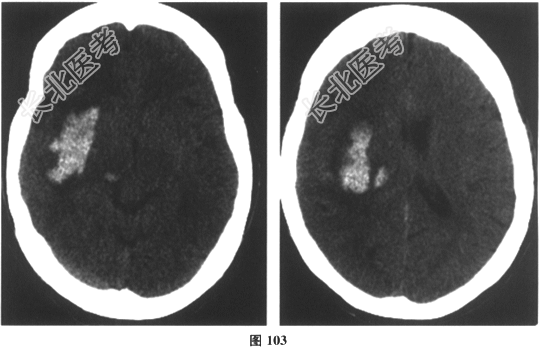

- 多项选择题6.[提示]急查颅脑CT,结果如图103所示。

该患者诊断为 A、急性脑梗死

B、急性脑出血

C、硬膜下血肿

D、脑疝

E、脑内钙化灶

F、脑卒中

G、TIA